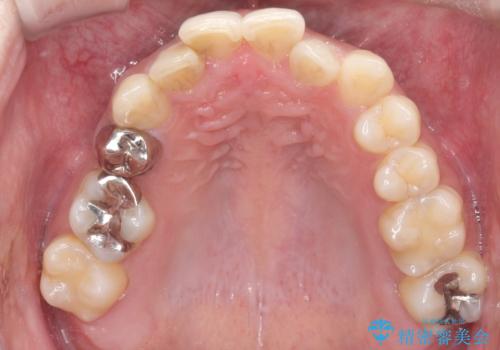

重度の叢生を抜歯矯正で改善|審美ワイヤー矯正+海外出張に伴う中断・再開対応

- 治療計画: 重度の叢生を改善するため、上下左右の小臼歯抜歯を伴う審美ワイヤー矯正を計画しました。抜歯により得られたスペースを利用して歯を整列させ、適切な噛み合わせを目指します。途中、患者様が1年間の海外出張となったため、一時的にワイヤーを外し、保定装置で現状維持を図りました。帰国後に再度審美ワイヤー矯正を再開し、仕上げ調整を行い治療完了を目指します。

重度の叢生により、抜歯を伴う矯正が必要と判断しました。目立ちにくい透明な審美ブラケットを用いたワイヤー矯正を実施しましたが、治療途中での海外出張が決定したため、一度矯正装置を取り外し、保定装置で現状維持を行いました。帰国後に改めて装置を装着し矯正を再開。患者様のライフスタイルに柔軟に対応しながら、最終的には理想的な歯並びと美しい口元を実現しました。